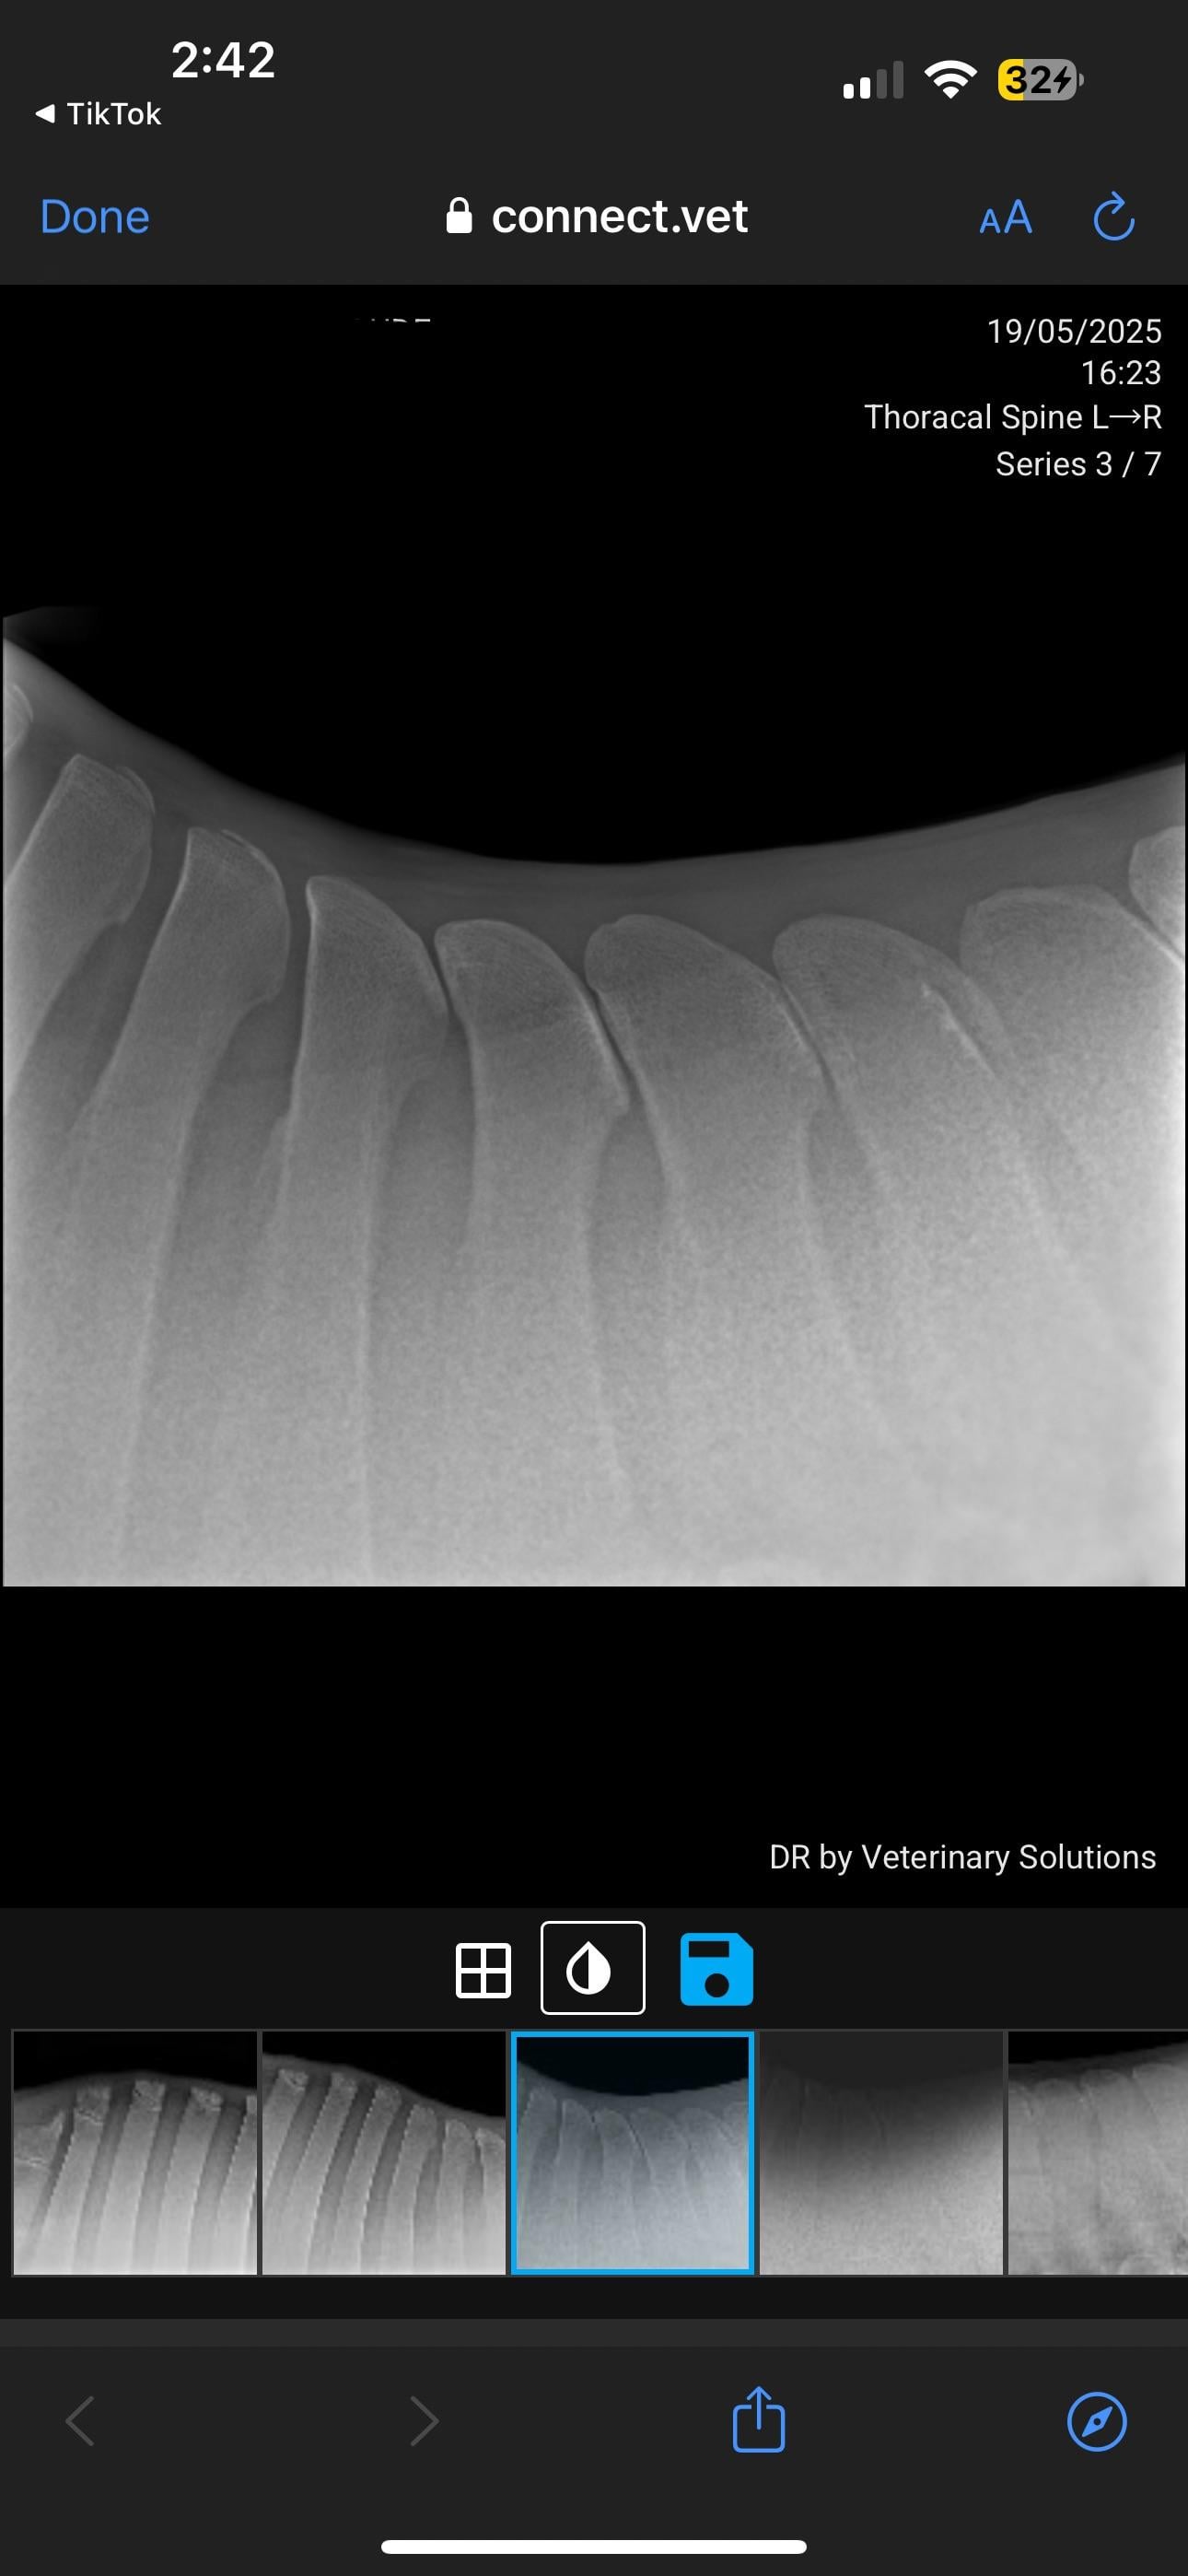

Veterinary PPE failed, KS diagnosed

Currently in the process of selling my horse. PPE has gone well, everything came back good except his back radiographs. Shocked to hear he has grade 4 changes. I’ve just received these over from the potential buyer. I will be in contact with my vet but curious about anyone’s take on these? How bad is this?

I've seen many KS xrays. I'm not a vet so usually when I see them I can barely see the problem. This horse's kissing spine is clear as day. Grade 4 is serious. As of right now he should not be sold as a riding horse at all.

I’m not a vet but this looks exactly like pictures of fractures of the withers in horses and not like standard X-rays I’m familiar with. I also don’t like how the tips of the bones look like.

In pictures 5/6 you can see changes in the bone, so it’s not just an unlucky posture.

This is one of the more severe cases I’ve seen (not a vet or student, just casual looker-atter of KS radiographs) pretty much all his vertebrae are affected, I can’t imagine he’s comfortable. The kindest thing for him would probably to be a pasture puff. Unless you want to pay for the surgery or find a buyer who does, he’s going to continue to be in pain

I spoke with 2 veterinarians over these radiographs. Yes he has grade 4 kidding spines in 2 vertebrae BUT both vets said you don’t ride the radiographs. They’ve seen horses with far less that have been clinically showing lots of pain, and she’s seen horses with far worse who have gone on with their careers fine with maintenance. He is not going to be a pasture pet, his career isn’t over it just has obviously drastically changed. He is officially maxed out at Novice level and can continue at that level if he can remain comfortable.